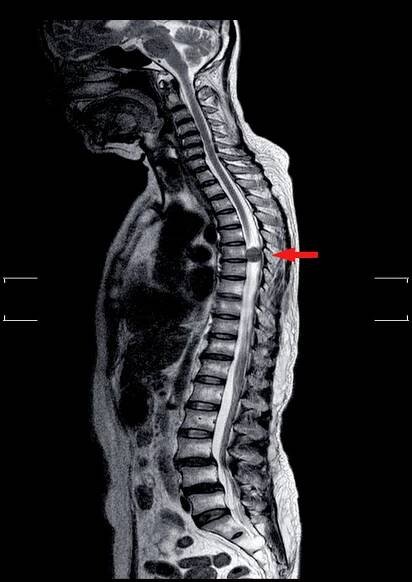

MRI THORAKOLUMBÁRNÍ ŠPINY Snížená lumbosakrální lordoza bez spondylolistézy.Středně patologická komprese hladin T11 a L2 se zvýšením mnohočetných lézí dřeně na hladinách T1, T10 až T12, L2, L3 až L5. — Stock obrázek